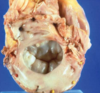

What is your Dx? How do you know this?

Fibrocalcific aortic stenosis - you know it isn’t rheumatic heart disease because there is no commisural fusion